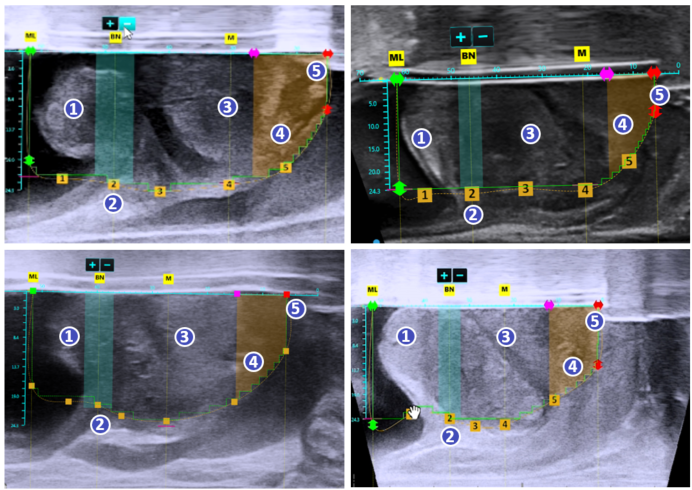

아쿠아 블레이션 수술 과정

초음파와 내시경을 동시에 실시간으로 확인하며 절제할 조직과 보존할 조직을 정확히 설계

수술 전 막혀있는 전립선 초음파 소견

수술 후 잘 열린 전립선 초음파 소견